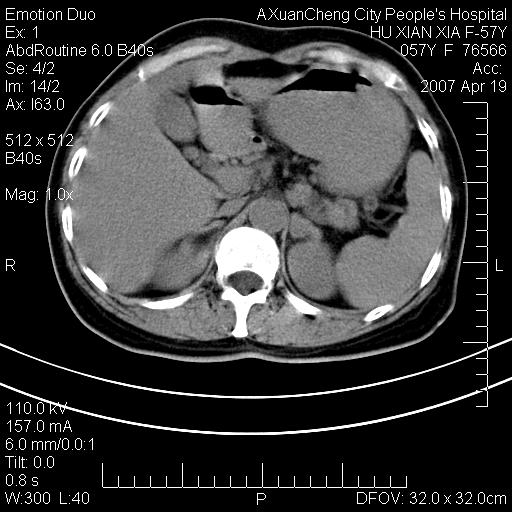

标题: CT7778:[原创]F,57Y腹痛待查,胸片提示肺部占位,应当很典型 [打印本页]

标题: CT7778:[原创]F,57Y腹痛待查,胸片提示肺部占位,应当很典型

胸片提示肺部占位

考虑:1、双侧肾上腺占位.2、肝左叶内侧段不规则低密度灶,建议强化扫描.

忽略了,只以为急腹症,应该支持肺癌肾上腺转移,肺癌患者20-30%发生肾上腺转移

双侧肾上腺增大,有分叶,密度均匀,考虑转移建议查原发灶

1.双侧肾上腺占位,转移首先考虑。

2.肝硬化,门静脉高压;肝左叶内侧段病灶建议增强。

3.12指肠水平段狭窄,建议行低张12指肠造影。

支持肺癌肾上腺转移,肺癌患者20-30%发生肾上腺转移

双侧肾上腺结节样肿块,结合肺部肿块,考虑肺癌肾上腺转移。

双侧肾上腺及腹膜后淋巴结增大,结合胸片提示肺部占位,考虑肺癌双侧肾上腺及腹膜后淋巴结转移.